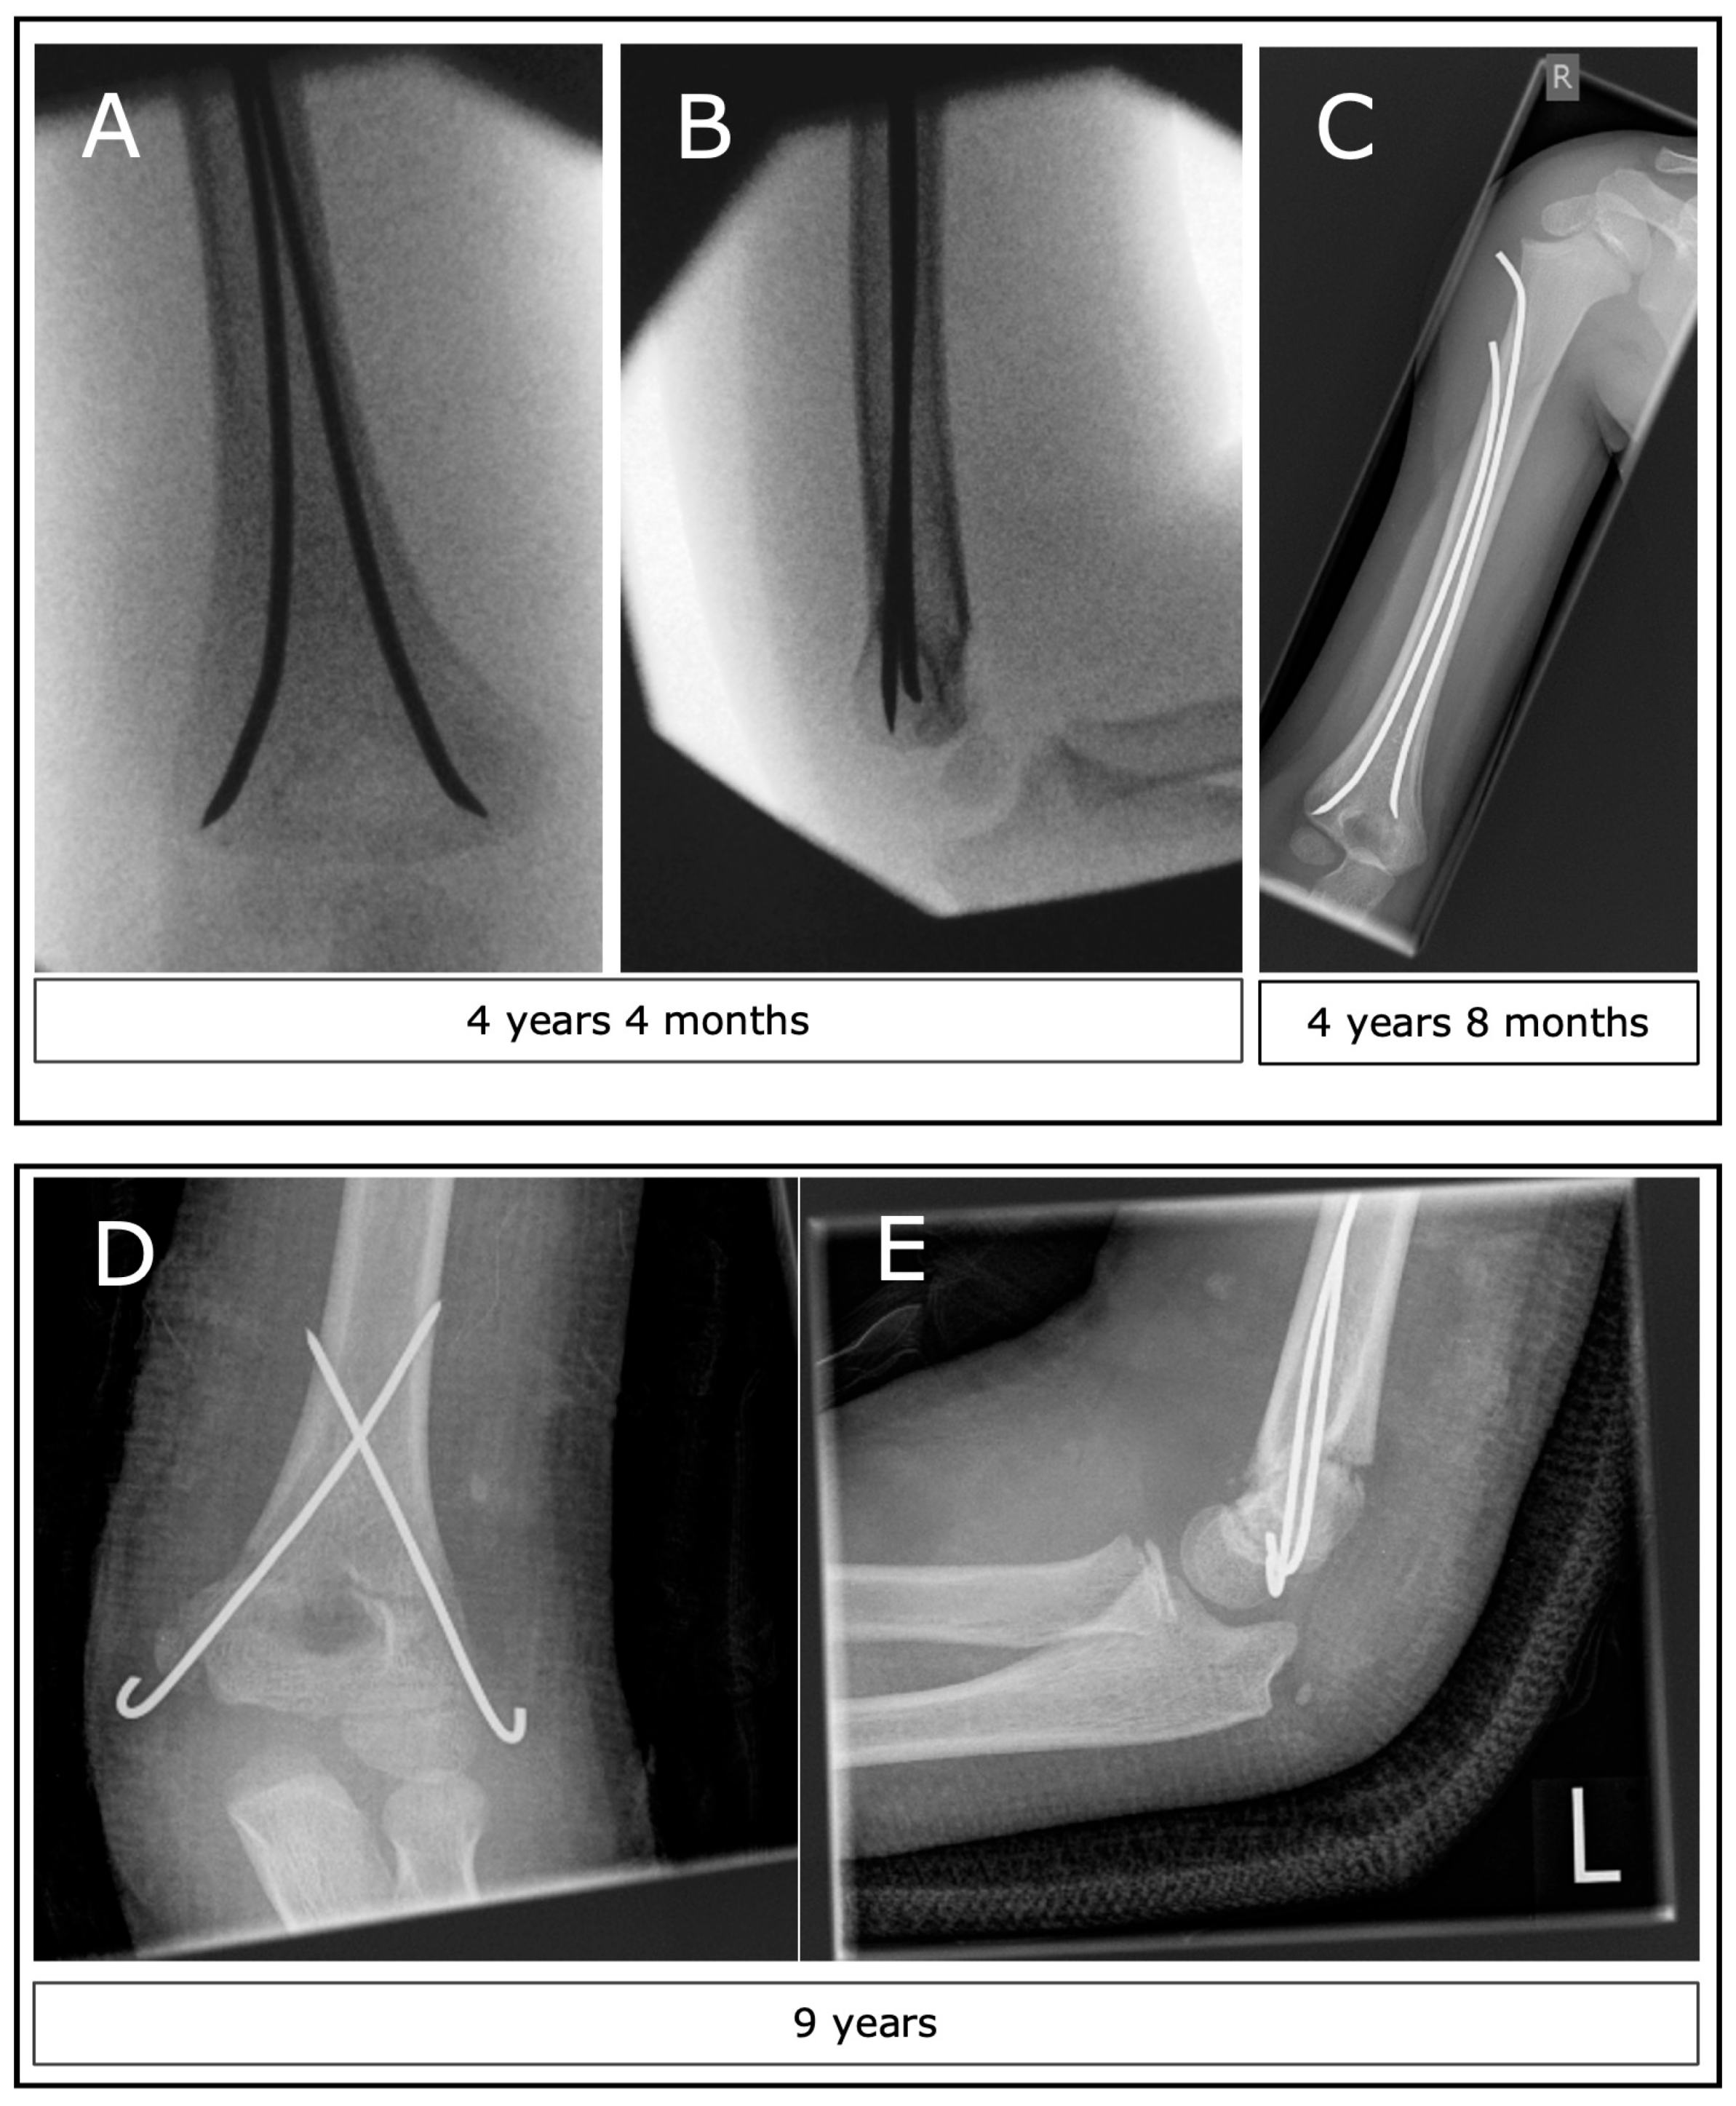

Figure 1.

Two examples of surgical methods for SCHF. (A,B) Intraoperative images of a patient with a type II SCHF after closed reduction and ESIN. (C) The condition 4 months after surgery and before implant removal. (D,E) Images 1 week after open reduction and K-wire osteosynthesis plus plaster.